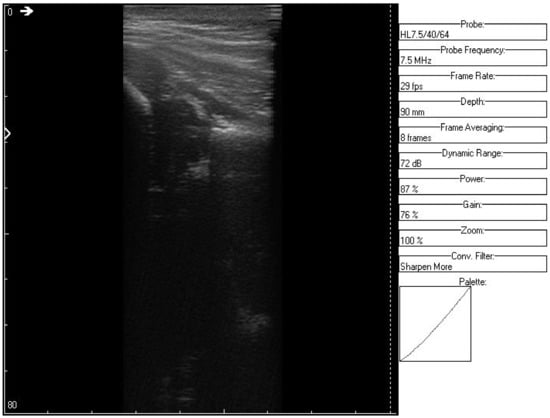

An ultrasound (Image 3 (Figure 10 and Figure 11)) was taken of a male patient with a sample frequency of 7.5 MHz and a frame rate of 29 fps. The parameters are same as in the previous two cases, yet the image of the acetabulum is hardly visible.

After applying the HWT filtering (Figure 12), the acetabulum, the femoral head, and the femur can be outlined by any physician.

We may conclude, when comparing last two images, that after filtering several details can be seen, easing the process of diagnosis for a trained physician. The denoised images are brighter and more details (not visible on the original image) can be distinguished.

Figure 10. Original data, Image 3.

Jpm 12 01328 g010